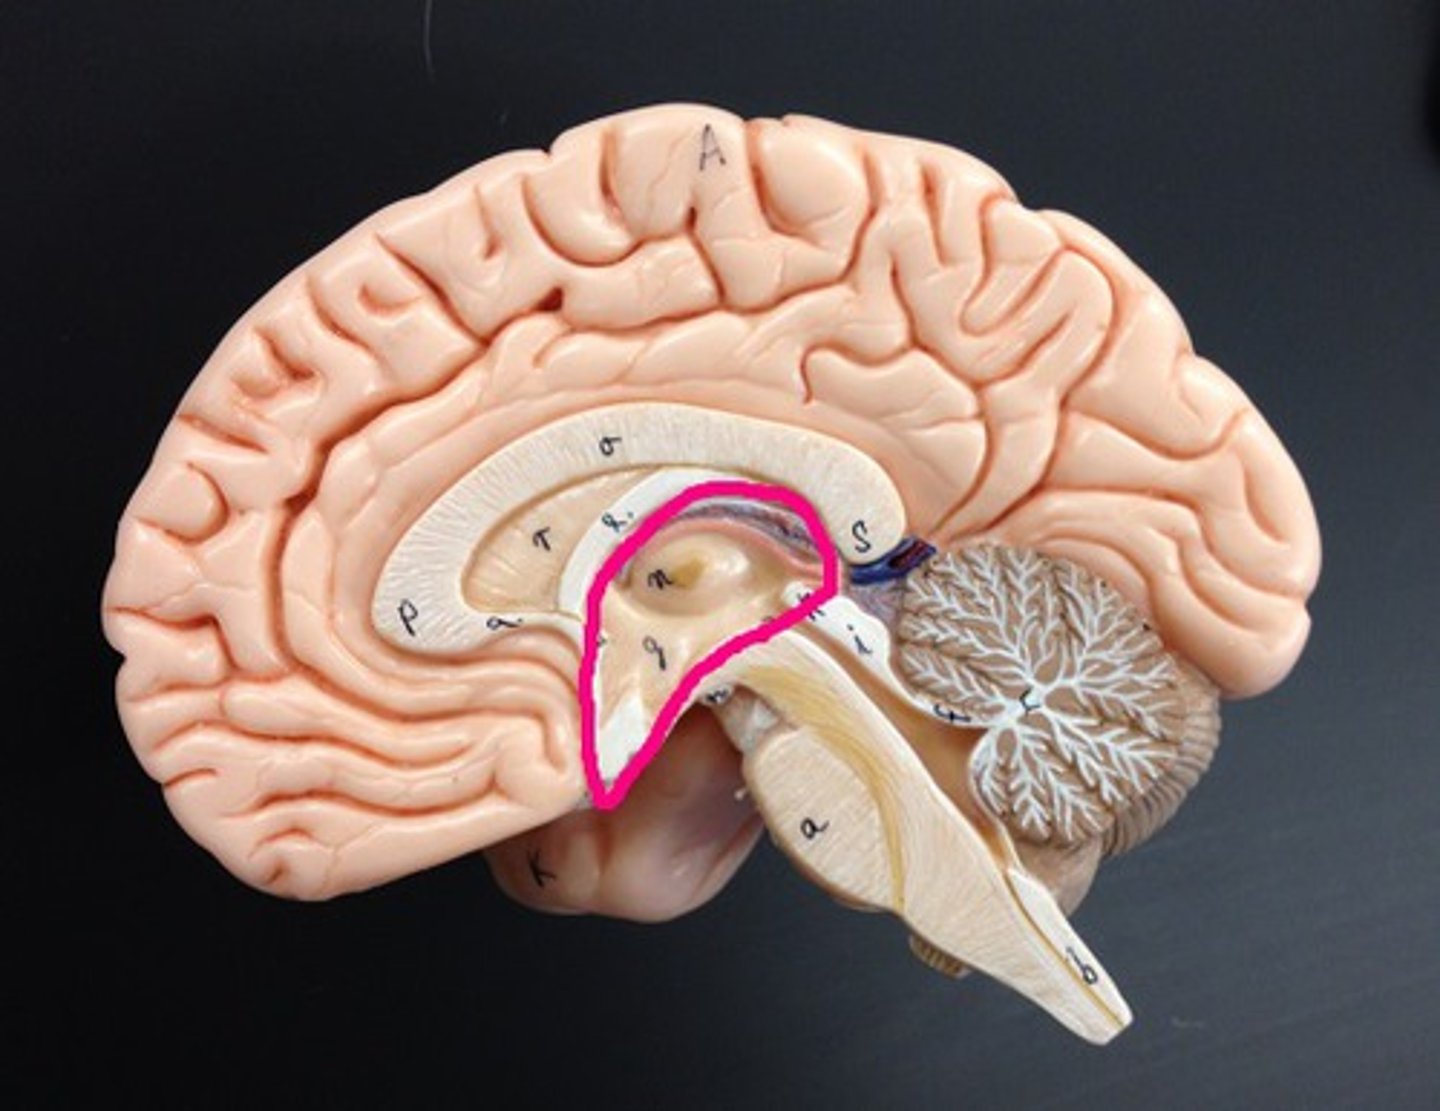

Circulation of CSF

CSF from the lateral ventricles → interventricular foramina → third ventricle → cerebral aqueduct → fourth ventricle → subarachnoid space or central canal.

corpus callosum

broad band of white matter containing axons that extend between the cerebral hemispheres

limbic system

a rung of structures that encircles the upper part of the brainstem & corpus callosum inside of the cerebrum & floor of diencephalon